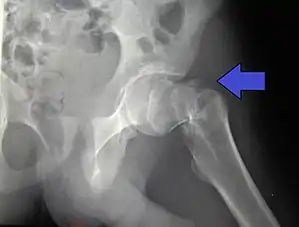

A hip fracture is a break that occurs in the upper part of the femur (thigh bone), at the femoral neck or (rarely) the femoral head.[2] Symptoms may include pain around the hip, particularly with movement, and shortening of the leg.[2] Usually the person cannot walk.[3]

| Intertrochanteric hip fracture in a 17-year-old male | |

X-rays of the affected hip usually make the diagnosis obvious; AP (anteroposterior) and lateral views should be obtained.